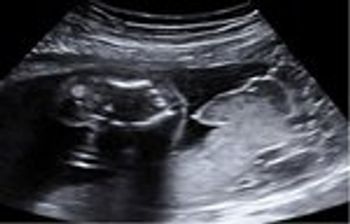

Here are two ultrasound images taken during the 3rd trimester of pregnancy.

What is your diagnosis of this 3rd trimester ultrasound?

The perinatologist found a jaw abnormality on ultrasound but failed to diagnose the disorder. Read the facts, and see what you think.